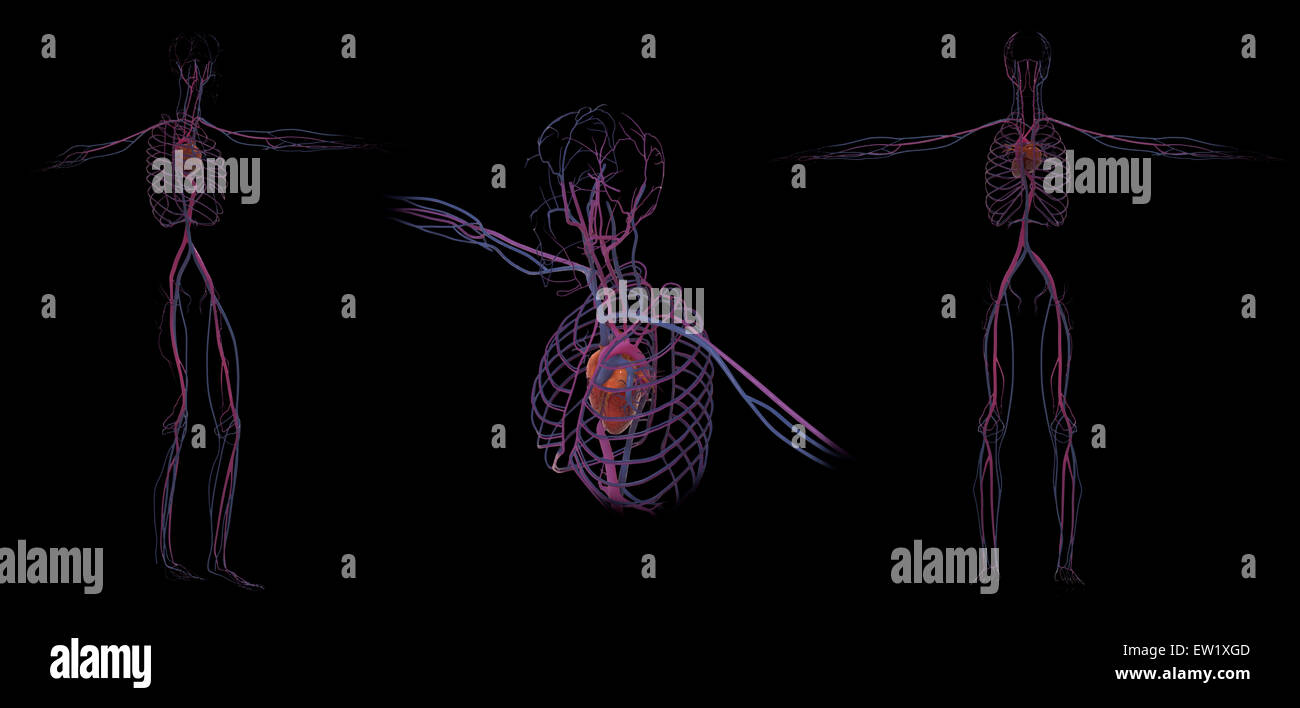

3D rendering of human circulatory system. Stock Photohttps://www.alamy.com/image-license-details/?v=1https://www.alamy.com/stock-photo-3d-rendering-of-human-circulatory-system-84250669.html

3D rendering of human circulatory system. Stock Photohttps://www.alamy.com/image-license-details/?v=1https://www.alamy.com/stock-photo-3d-rendering-of-human-circulatory-system-84250669.htmlRFEW1XGD–3D rendering of human circulatory system.